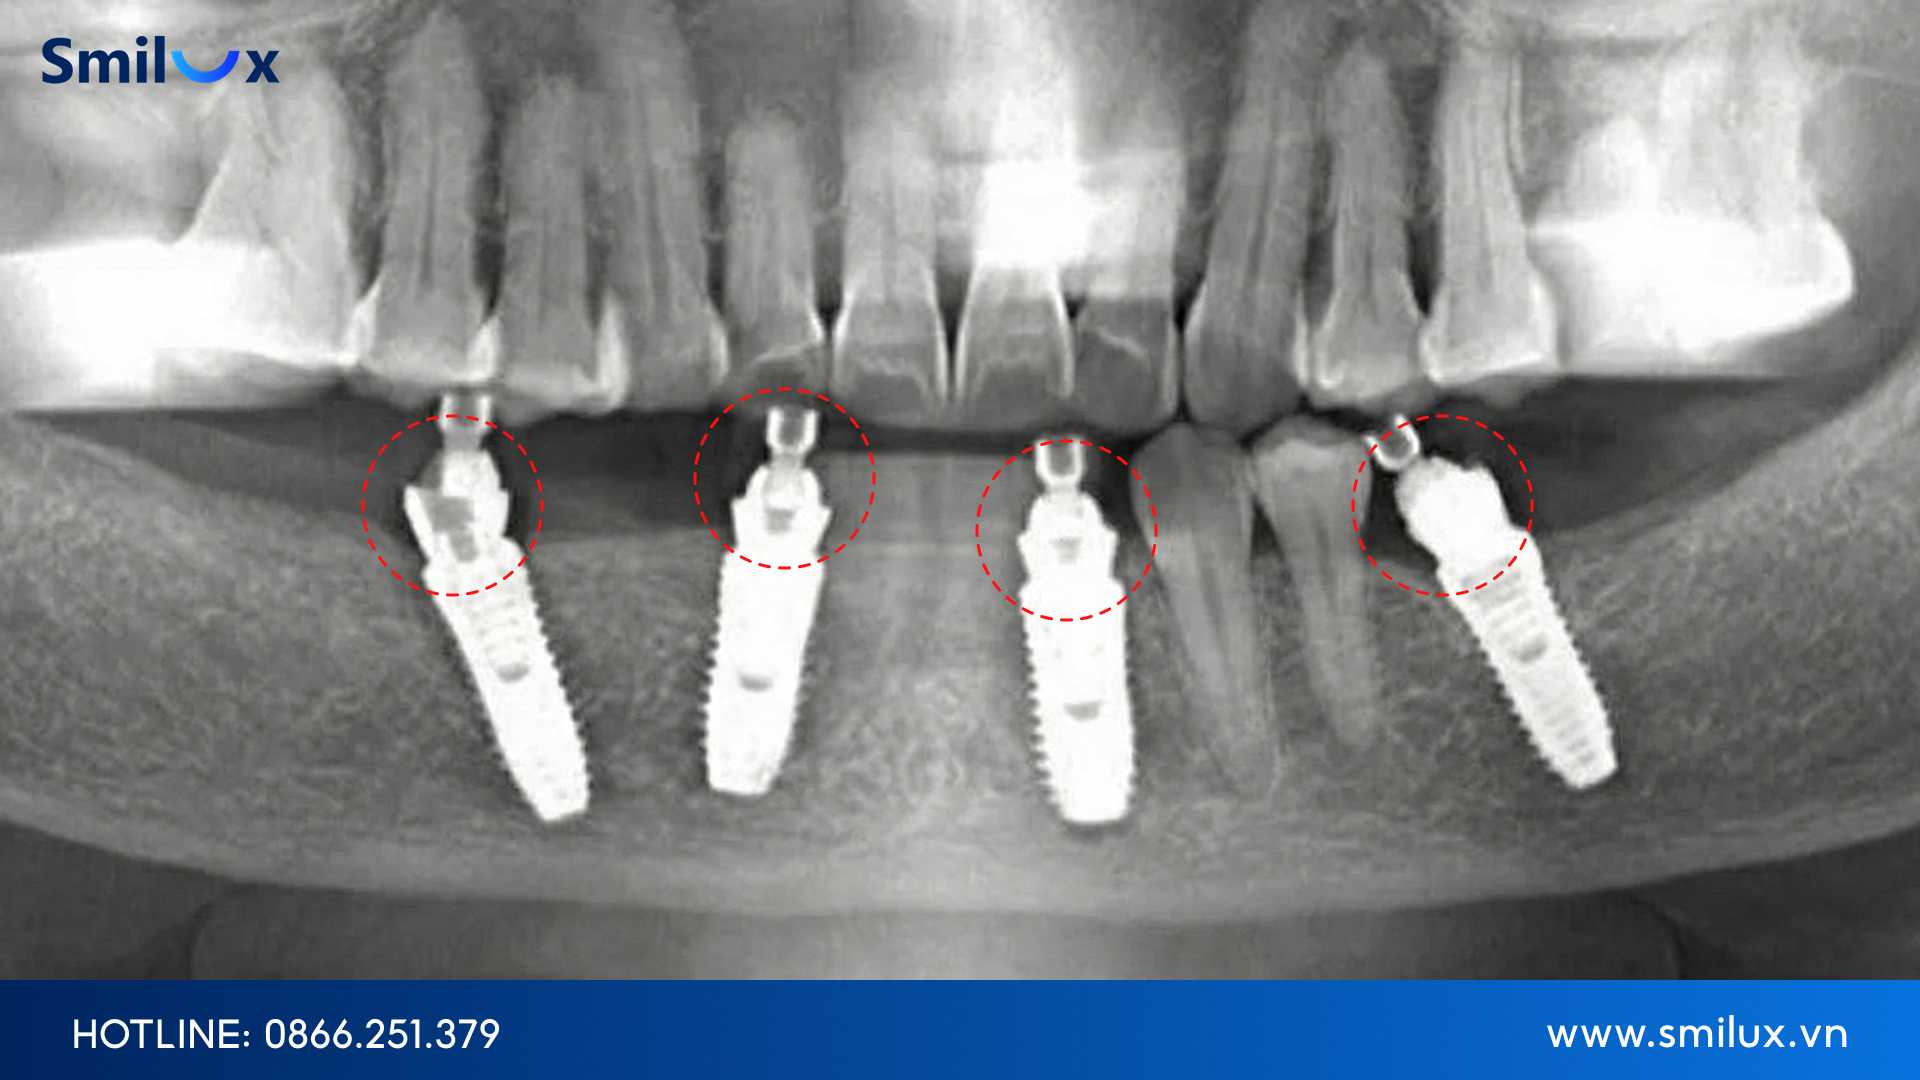

Nhiều người chỉ quan tâm tới lợi ích như ăn nhai chắc chắn, răng bền lâu, không cần tháo lắp…, mà quên rằng trồng Implant toàn hàm là một quy trình phức tạp. Không giống như việc trồng một vài trụ đơn lẻ, toàn hàm yêu cầu sự phối hợp chuẩn xác từ việc khảo sát xương hàm, đo mật độ xương, xác định vị trí đặt trụ đến việc cân đối toàn bộ khung răng. Khi những bước này bị bỏ qua hoặc thực hiện không đúng, rủi ro tăng dần theo từng giai đoạn.

Một trong những biến chứng thường gặp là nhiễm trùng sau phẫu thuật. Nguyên nhân có thể đến từ việc vô trùng chưa kỹ, xương hàm không đủ điều kiện để tích hợp Implant, hoặc do chế độ chăm sóc hậu phẫu không đúng. Khi vùng cấy ghép bị nhiễm trùng, quá trình lành thương bị gián đoạn, Implant khó kết hợp với xương hàm và có thể dẫn đến thất bại điều trị.

Bên cạnh đó, tổn thương dây thần kinh và xoang hàm cũng là rủi ro mà không ít bệnh nhân gặp phải khi vị trí đặt trụ không được tính toán chuẩn xác. Hiện tượng này có thể gây tê kéo dài, đau nhức hoặc cảm giác khó chịu thường xuyên nếu không được xử lý kịp thời.

Không chỉ yếu tố kỹ thuật, tình trạng xương hàm và sức khỏe tổng thể của người bệnh cũng quyết định rất lớn đến thành công của cấy ghép. Những trường hợp tiêu xương nặng, bệnh lý nền chưa được kiểm soát tốt hoặc không qua thăm khám đánh giá đầy đủ sẽ có nguy cơ Implant thất bại cao hơn. Điều này đòi hỏi người bệnh phải được bác sĩ tư vấn kỹ lưỡng trước khi quyết định điều trị.